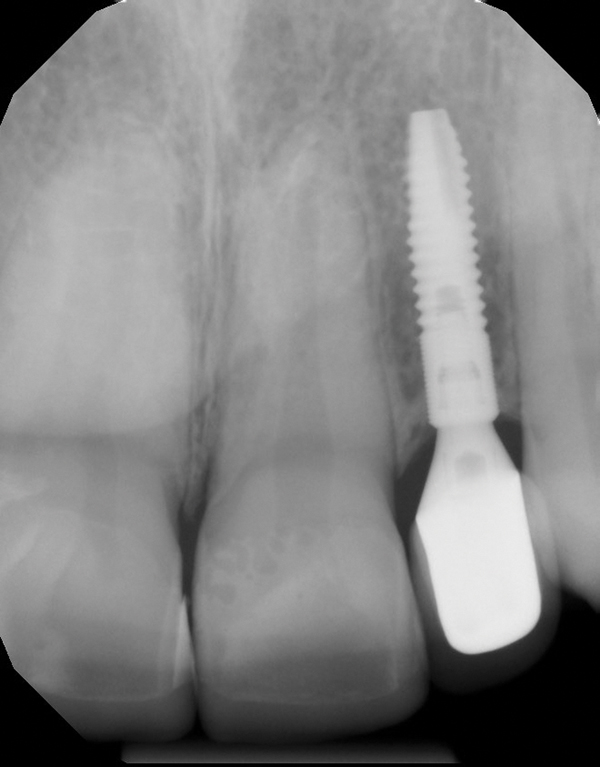

Fig 3. Radiographic scan of fused maxillary central-peg lateral incisors, teeth Nos. 7 and 8, and congenitally missing lateral incisor, tooth No. 10.

Figure 3

When the patient was 18 years old, an implant was placed in site No. 10 with no complications (Figure 9 and Figure 10). Three months later, a periapical radiograph was taken, the implant was torque tested, and a healing abutment (3 mm by 4 mm by 4 mm) was placed.